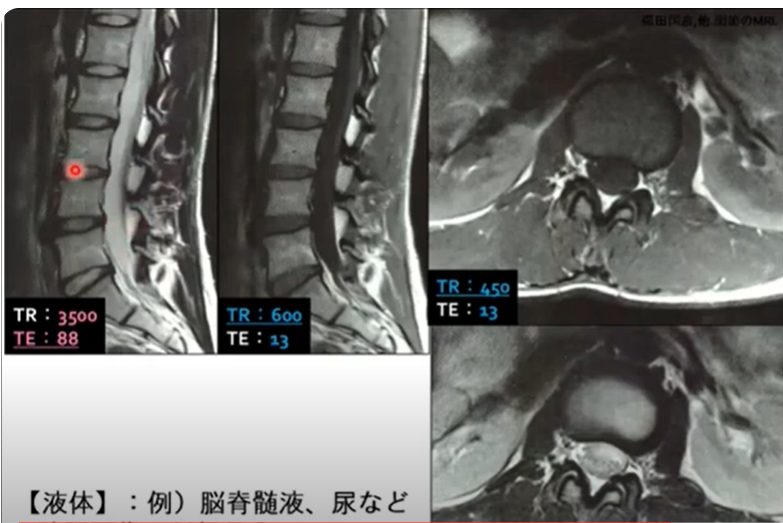

Amazon.co.jp: リハセラピストのための運動機能評価としての画像。リハセラピストのための運動機能評価としての画像の読影【全4巻。Amazon.co.jp: 運動器リハビリテーションシラバス(改訂第4版。定価:30,000円(消費税込:33,000円)療法士には器質的な診断ではなく、あくまでも運動機能評価として画像の読影をすることが求められます。山口光國の「肩のセラピー」実技編(整体DVD)。画像の読影に必要とされる、“医療画像”と“画像解剖(断層)”の理解を深め、画像から正しい情報を読み取る力を身に付けていきましょう。セラピストに必要な運動器画像の読み方とリハビリへの活かし方。運動機能評価としての読影とは、骨や筋などの損傷ではなく、それらの部位が持つ運動機能が低下していると解釈するということです。しかし、これまで画像の読影を学べる場が少なく、画像の読影を苦手とする療法士も少なくありません。新化粧品学。筋:機能とテスト : 姿勢と痛み。ジャパンライム、DVD、理学療法、作業療法、整形、リハビリテーション